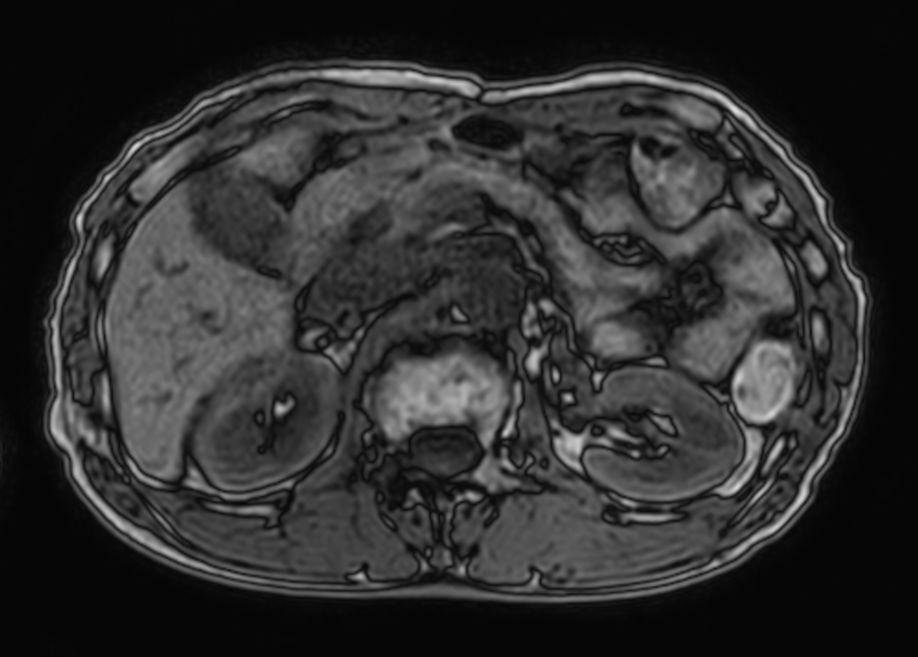

T1w FFE mDIXON XD- Compressed SENSE

-